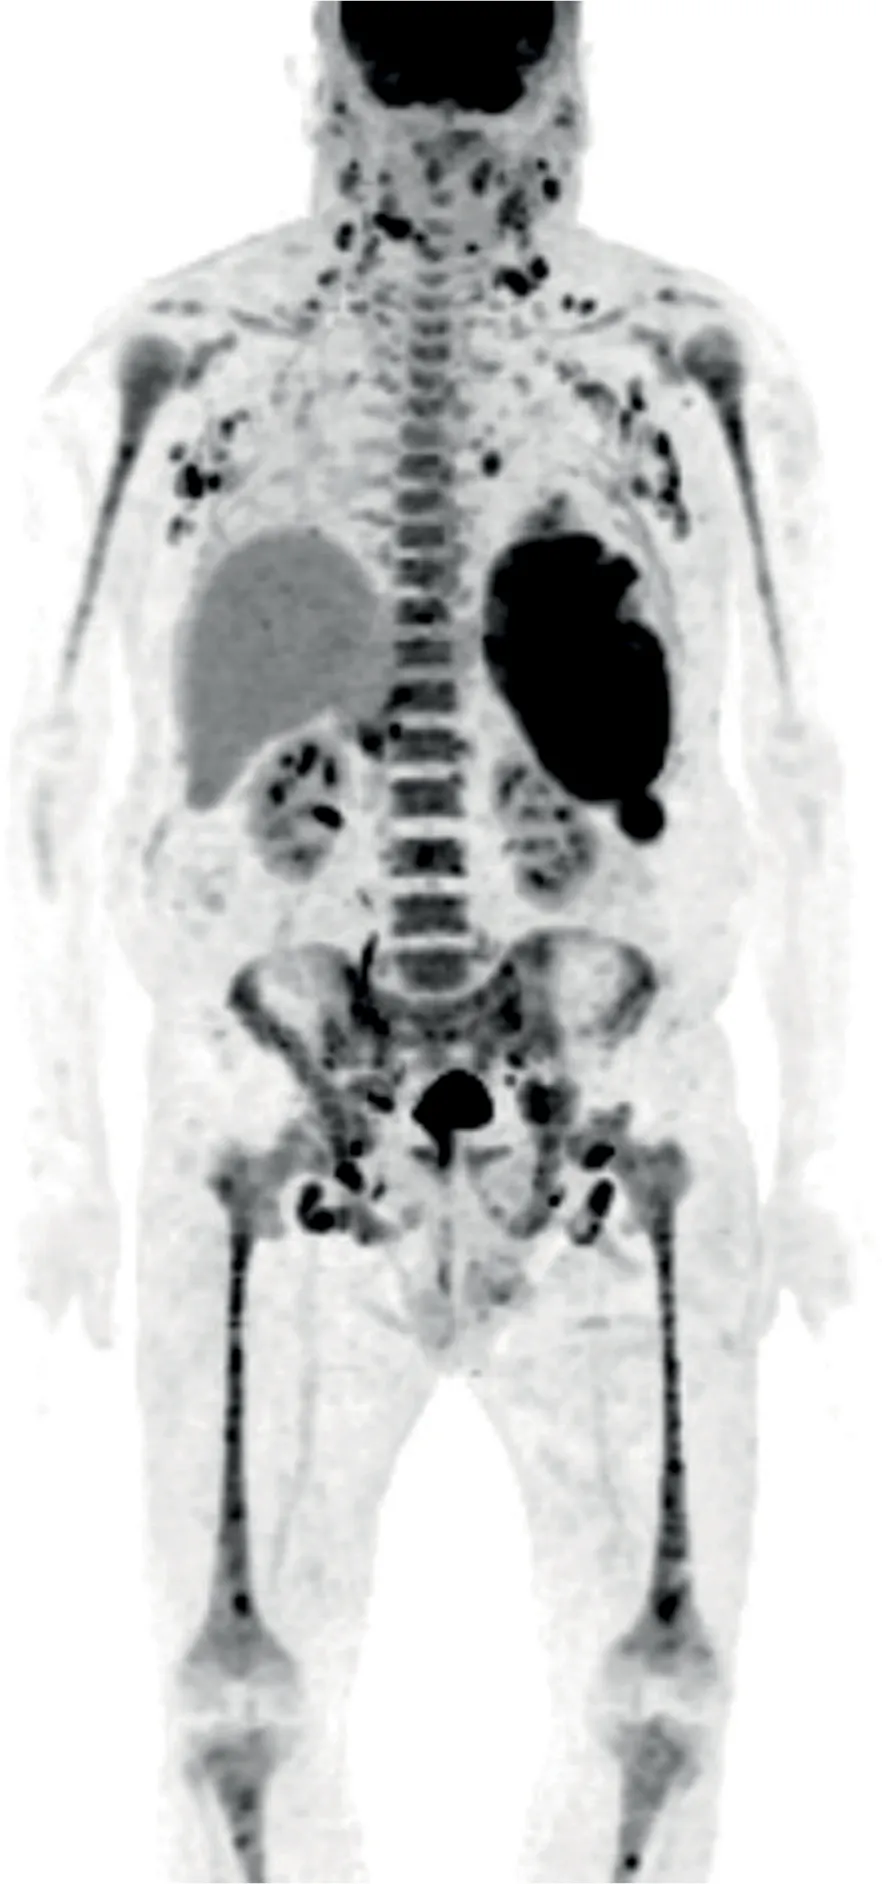

The involvement of other organs has no specific characteristics and is clinically perceptible or easily evaluated with CT or PET scans at the initial evaluation when patients are suspected of having BPDCN (Figure 2.4). PET is a good tool for the initial diagnostic staging of the disease, as it can then provide a useful evaluation of tumoral response thereafter.2,12

Figure 2.4 PET-CT scan of a patient with BPDCN at diagnosis, showing extensive organ involvement.